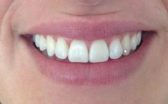

- After

At the end of four months, my front teeth were straight and I was able to have my braces removed! I am extremely happy with my Cfast end result and it was all worth it.